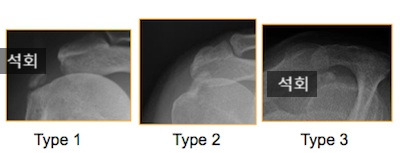

석회성건염은 어떻게 진단하나요?

특징적인 어깨 통증과 같은 증상과 엑스레이, 초음파 등으로 쉽게 확인할 수 있습니다.

엑스레이로 확인한 석회성건염